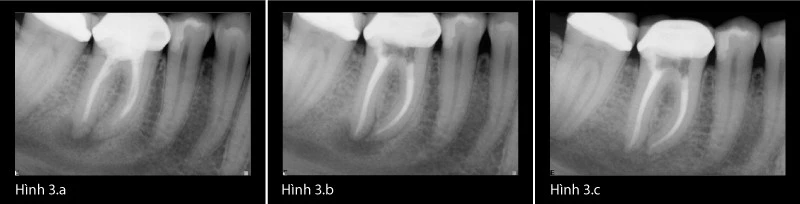

Natri hypochloride 6% là chất kháng khuẩn mạnh, có khả năng phân hủy mô và phá vỡ màng biofilm vi khuẩn.[20],[21] Những phẩm chất này của một chất bơm rửa là lí tưởng cho việc làm sạch vi khuẩn và mảnh vụn mô còn sót lại. Việc sử dụng đê cao su để cách li vùng điều trị là tiêu chuẩn của điều trị nội nha. Thất bại khi sử dụng đê cao su có thể góp phần chủ yếu gây ra bệnh lý sau điều trị. Những case sau đây minh họa khả năng vượt qua điều trị không đạt trước đó để lành thương thành công (Hình 3a-c).

Ví dụ lâm sàng